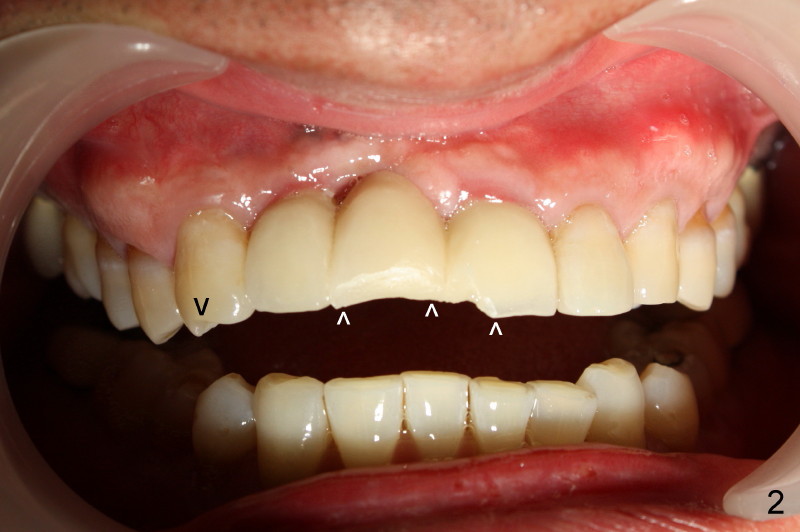

Fig.1 was taken when the new bridge was temporarily cemented (mirror view, Jan. 28, 2010). Arrowheads indicate enamel chip from the lingual cusps of the upper 2nd premolars. On Nov. 11, 2010, the bridge became loose again and was cemented permanently. Two months later (Jan. 27, 2011), porcelain chipped again as shown in Fig.2 and 3 (white arrowheads; black arrowhead points to wear facet of the tooth #6). The chipped bridge was removed.